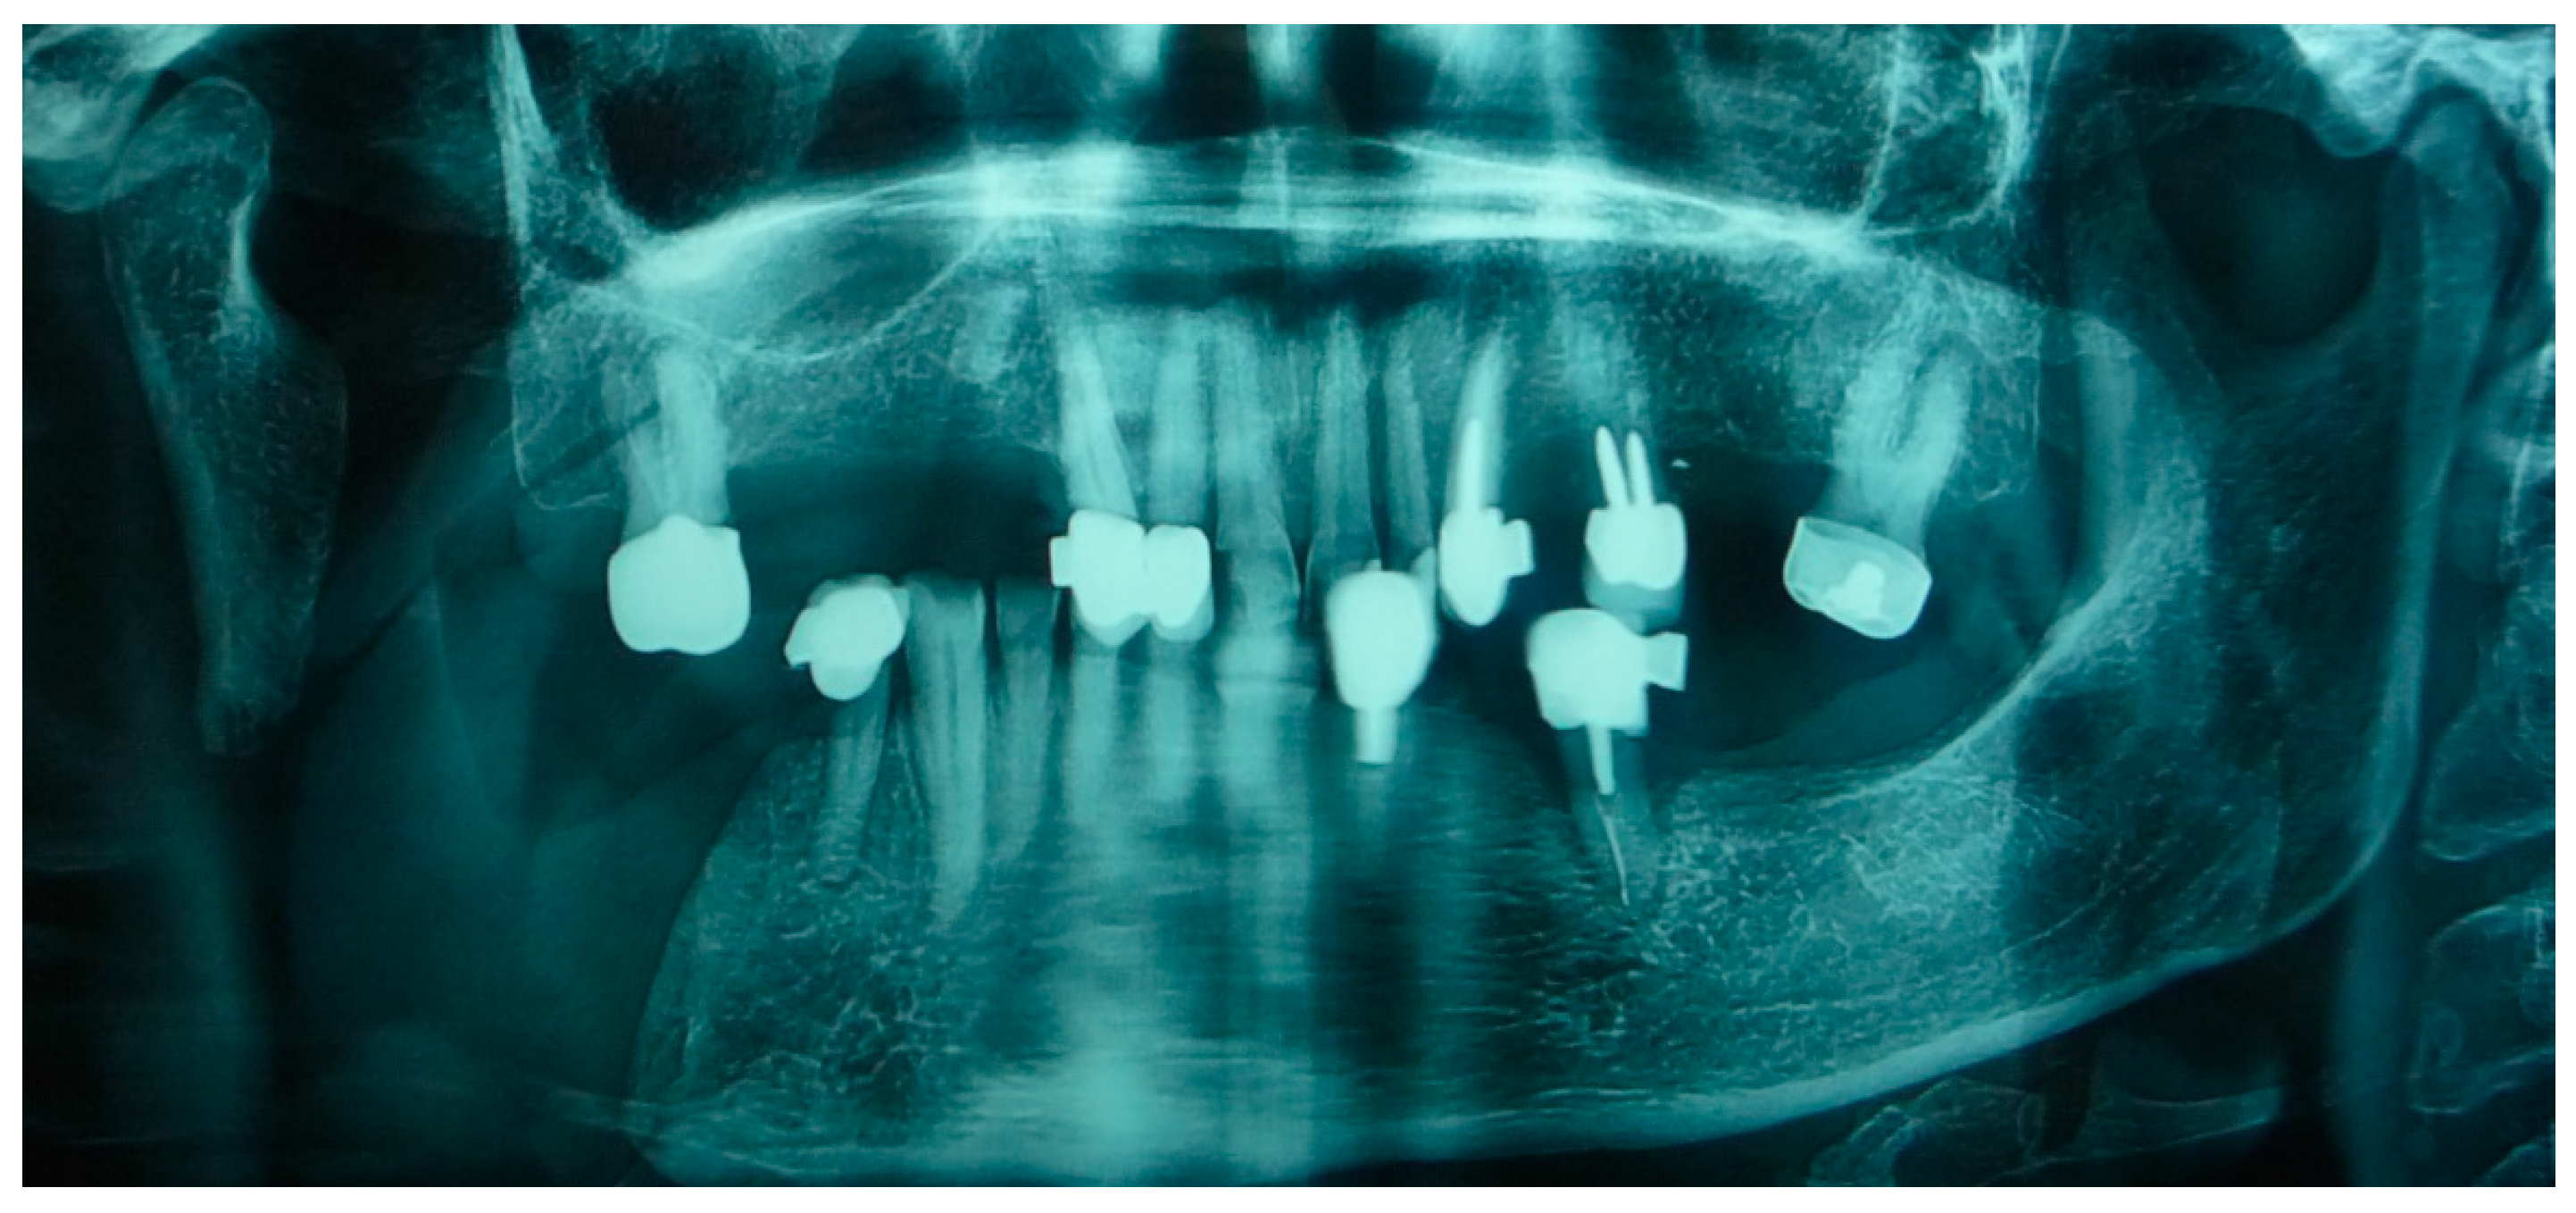

The patient in Case 1 had undergone surgery to remove a tumor that intersected the angle of the mandible. (L2) (Figure 1 and Figure 2). The upper elements were extracted soon after due to periodontal and endodontic issues. After being initially rehabilitated with a complete removable prosthesis (to regain function and aesthetic), two implants were subsequently placed in the 3.2 and 4.4 areas, and the final prosthesis was built in resin with a ball retention mechanism (Figure 3 and Figure 4).

The mandibular resection of this patient was not massive; hence, the rehabilitation project was in essence very similar to that of a normal edentulous patient, with the only exception of a rather extensive flange on the resected area to help stabilize the prosthesis during function.

Figure 2. Patient with hemimandibulectomy L2 in orthopanoramic X-ray.